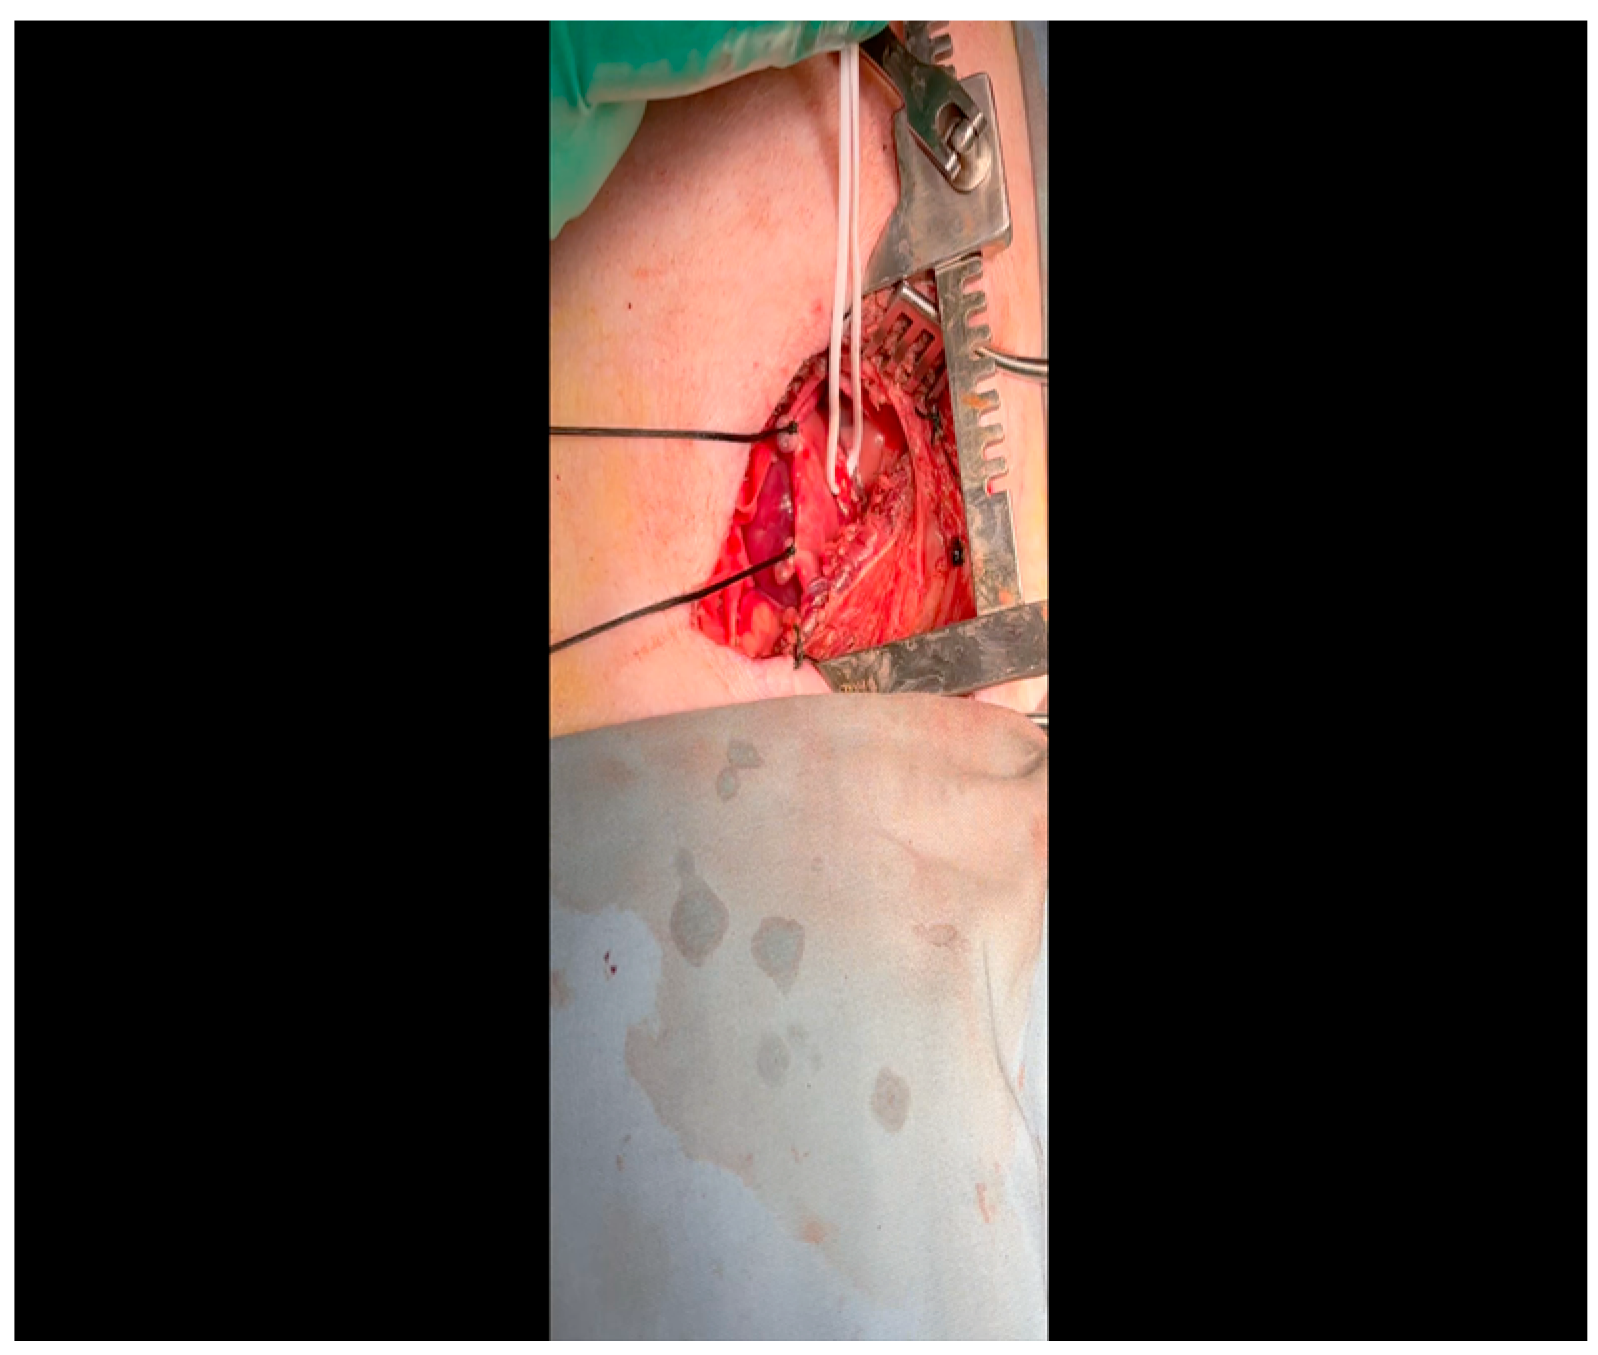

- A 3-0 silk suture secures the pericardium to the skin, elevating the heart into the surgical field and retracting the pericardium (Figure 4).

- Twenty mL of blood is withdrawn from the left atrial appendage to be sent for baseline metabolic parameters prior to treatment, as needed. A Satinsky clamp is used to isolate the puncture (Figure 5), a 2-0 silk tie is placed around the clamp to ligate the puncture, and a small hemostat is applied to the tie pull the appendage out of the surgical view.